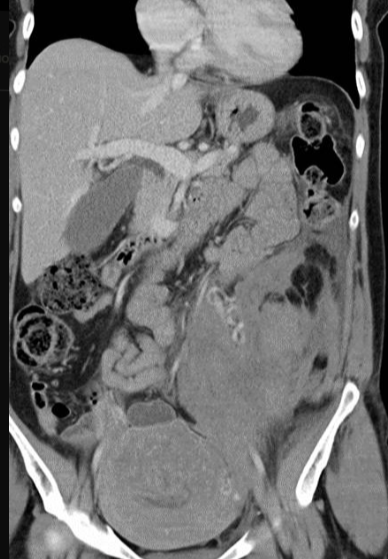

所有年龄超过 40 岁的患者, 卵巢受损 14%-43% 研究中闭经发生率(15%)与单纯UAE报告相似,可能与患者年龄(≥45岁)及卵巢储备自然下降有关。 ![]() 50岁,长期因子宫肌瘤导致月经出血过多,痛经和贫血。 子宫肌瘤栓塞术前,显示双侧子宫动脉发育不全,子宫肌瘤双侧卵巢动脉。 经皮股动脉穿刺双侧卵巢动脉栓塞,先500μm-700μm emboSphere 微球 术后4周,和6月的中短期随访,月经正常,子宫容积减少,贫血纠正,无卵巢功能衰竭。但看起来非灌注容积较少。 术后9月,由于子宫肌瘤持续存在,患者自己希望绝经,行全子宫和双侧卵巢切除术 术后病理,子宫内可见栓塞微粒伴有坏死,卵巢内也见栓塞微粒,但卵巢功能未受损。